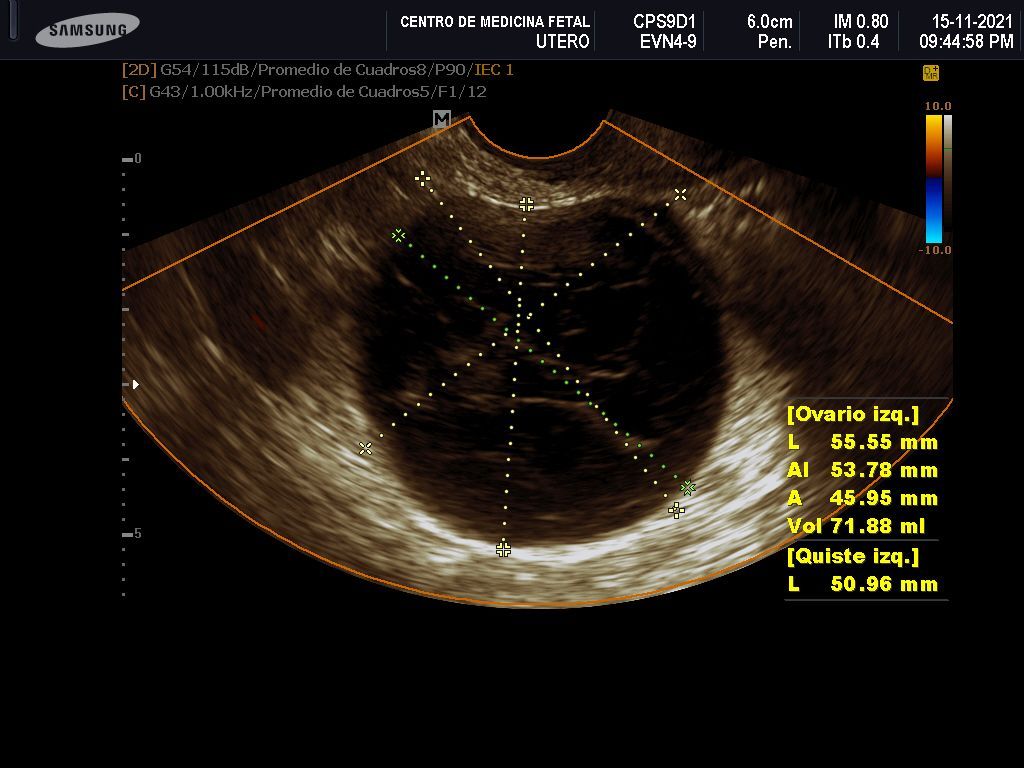

- Detección ecográfica transvaginal o pélvica y tratamiento de: Miomas, quistes de ovario, endometriosis, malformaciones uterinas